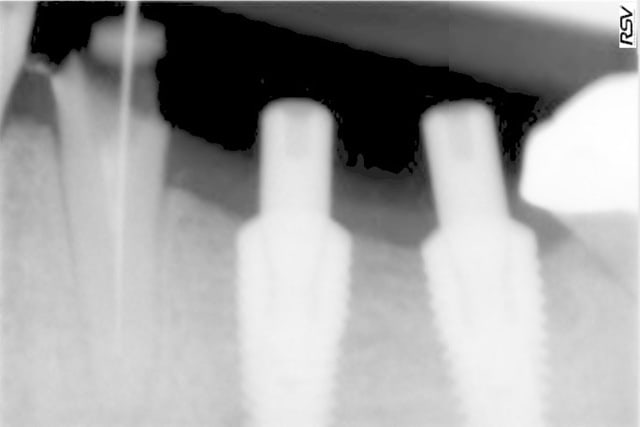

tous mes implants sont ostéo-intégrés, mais je trouve que la cratérisation est très importante et surtout très rapide.

donc pour moi, il y a un problème même si le taux de succès est de 100% en 2 ans.

Il manque les radios du jour de la pose, j'ai l'impression que les implants ne sont pas assez enfouis . Pa exemple Anthogyr recommande de poser l'Axiom 0.5mm en sous crestal, que préconise Tekka ?

En ce qui concerne la radio de la 21 , on dirait qu'il a été mis dans un site d'extraction et qu'il n'est pas assez large.

voici les radios le jour de la pose

le krestal doit être en crestal et non en infra-osseux: il s'agit d'une connectique à plat et non d'un cône morse.